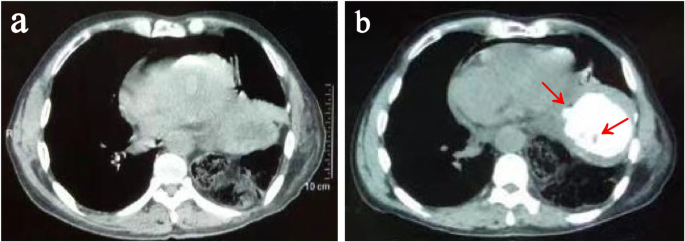

A 72-year-old man, who had radical esophagectomy (Sweet approach) for esophageal cancer 18 years ago, was presented to the emergency department with 1 day of nausea, vomiting and acute left chest pain. Computed tomography (CT) revealed a diaphragmatic hernia and air collection within the pericardial space (Fig. 1a). Oral meglumine amidotrizoate was taken by the patient; however, the following CT did not reveal any contrast agent leak into the pericardial space, while a gastric wall ulcer and an unspecific low density in the thoracic gastric cavity were noticed (Fig. 1b). At the emergence room, his heart rate was 110, BP was 93/68 mmHg and labs showed HGB 101.8 g/L, WBC 11.1 × 109/L, NE 10.18 × 109/L, NE% 91.2, RBC 3.97 × 1012/L. Based on these results, a diaphragmatic hernia could be diagnosed, but the etiology of the presenting pneumopericardium was unknown. Given that the diaphragmatic hernias needed urgent surgery and that they were possibly related to the pneumopericardium, we repaired them with a right transthoracic approach and found that there was no strangulation of the intestines. The patient recovered quickly after surgery until, on the third postoperative day, he complained of new chest pain. New CT was ordered and showed moderate pericardial effusion and right pleural effusion, which led us to suspect the existence of a thoracic gastropericardial fistula (Fig. 2a). The following contrast roentgenogram confirmed the thoracic gastropericardial fistula (Fig. 2b). A 1 cm diameter fistula tract was observed in the resulting pericardium surgery through the left thoracotomy (Fig. 3a). In the surgery, we removed a nearly 5 cm diameter pericardium around the fistula and part of the gastric wall, and we found two bezoars in the gastric tract (Fig. 3b-c). After we took out the bezoars and placed a jejunal feeding tube, we repaired the gastric wall and covered it with mediastinal fat tissue. Finally, a fine tube was placed in the pericardium for the purpose of postoperative rinsing and a drainage tube was also placed at the pericardial defect region. With the daily pericardial flush, the patient recovered quickly after starting to take oral food on the seventh postoperative day.